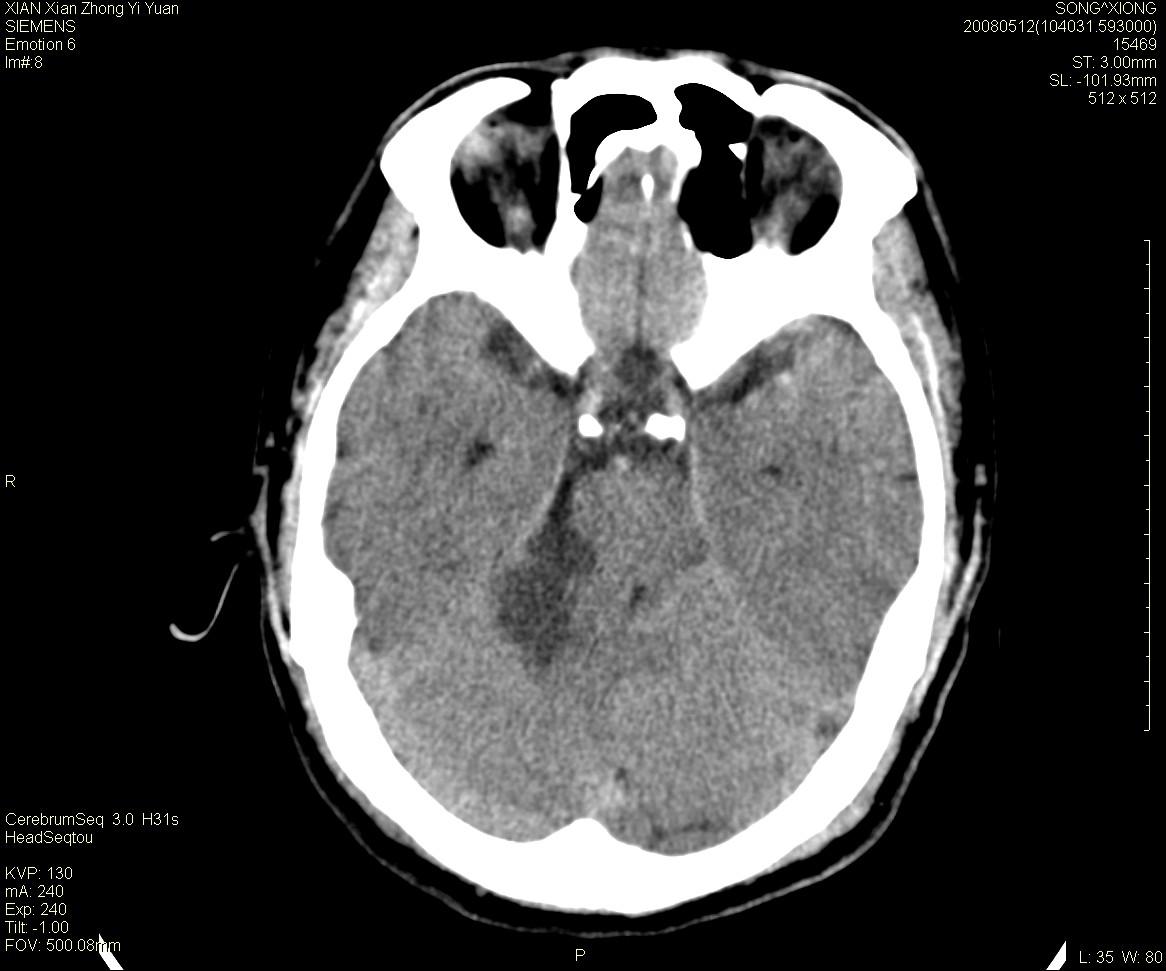

右侧内耳道慢性增宽,内耳道口出可见稍高密度影,桥小脑角池可见以较大低密度影,内缘较清,小脑、脑干、第四脑室受压、移位。

考虑:听神经瘤。

典型的右侧听神经瘤。